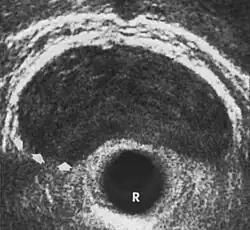

Ultrasonografia przezodbytnicza (strzałkami zaznaczono rak stercza)